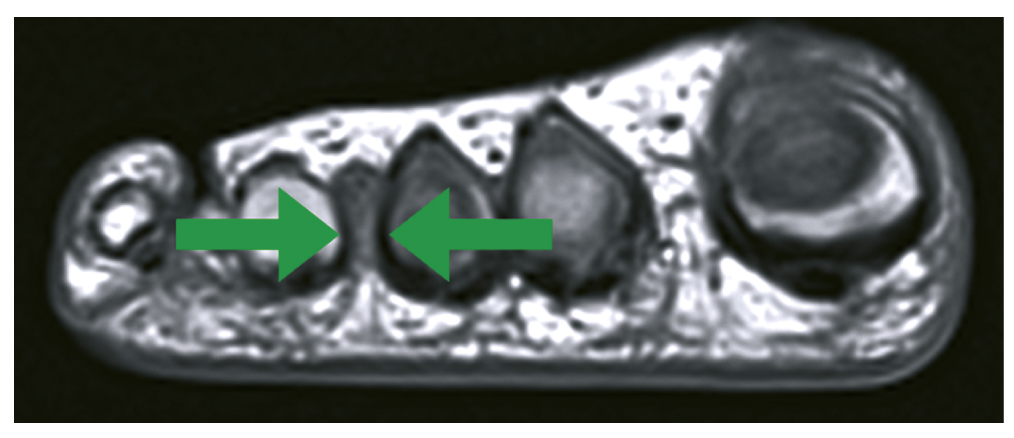

Протокол МРТ включал получение изображений в трёх плоскостях: прямая коронарная, прямая сагиттальная и аксиальная. Были выполнены серии МРТ, взвешенных по Т1-ВИ и Т2-ВИ, в трёх проекциях с жироподавлением (рис. 1, 2).

Рис. 1. Изоинтенсивный и гиперинтенсивный сигнал по сравнению с мышцами на Т2-ВИ в режиме FS (жироподавления) в III межпальцевом промежутке.